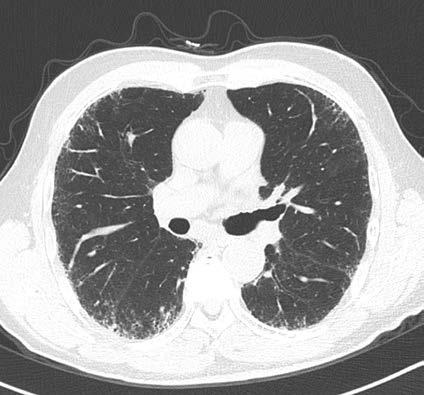

A doctor will also use a special kind of X-ray of the chest, called a high-resolution computed tomography (HRCT) scan, so that they can see what your lung tissue looks like. HRCT scans give a close-up view of the lungs, providing more detail than routine CT scans (also known as CAT scans). Healthy lung tissue looks nearly black on a CT scan. Scar tissue and inflammation both appear grey or white. Many forms of PF look similar on a CT scan to the untrained eye (see page 12), but subtle findings on HRCT scans are critically important when trying to identify which type of PF you have. An HRCT protocol recommended by the PFF and PF experts is available on the PFF website. Sometimes, even after all of the testing is complete, a doctor will still not have an answer and will have to perform a lung biopsy to sort out which of the 200 different types of PF you have. When indicated, a lung biopsy can also help you and your doctor decide which treatments might be helpful.

Normal Lung

On CT imaging, lung slices are obtained from the neck through the stomach similar to slicing a loaf of bread. Air is typically black as noted by the air above the chest and throughout most of the lung in the normal patients. With abnormalities such as inflammation or fibrosis in the lung, varying degrees of white opacities are noted in the lung with structural changes such as honeycomb change or traction bronchiectasis.

Reticulation – extra lines in the lung

Honeycomb – distorted, end stage fibrotic lung

Ground glass – nonspecific abnormality that may reflect inflammation, fibrosis, bleeding, fluid in the lung.